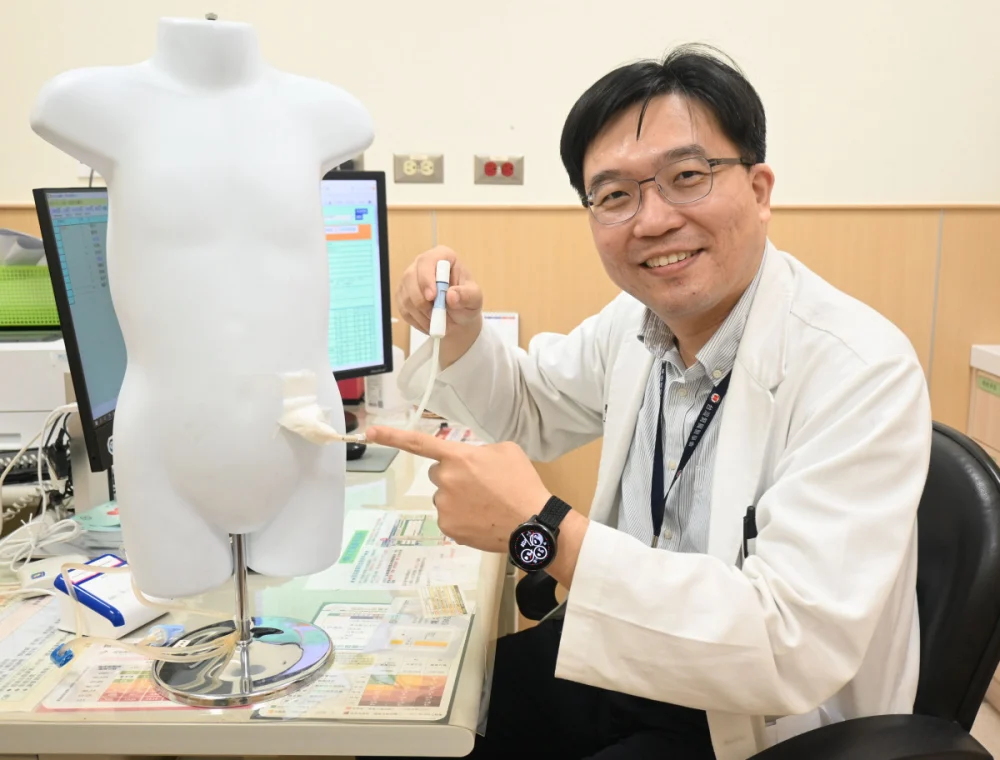

揮別攝護腺癌 「海扶刀」精準定位消融癌細胞

記者季大仁/新竹報導東元醫院泌尿外科戴順慶醫師利用「海扶刀(HIFU)高強度聚焦超音波微創手術」幫助多名攝護腺癌病人,揮別早期攝護腺癌症陰霾。攝護腺癌呈現年輕化,正值壯年的病人而言,如何在根除癌症的同時保留生活品質是關鍵。東元綜合醫院泌尿外 …